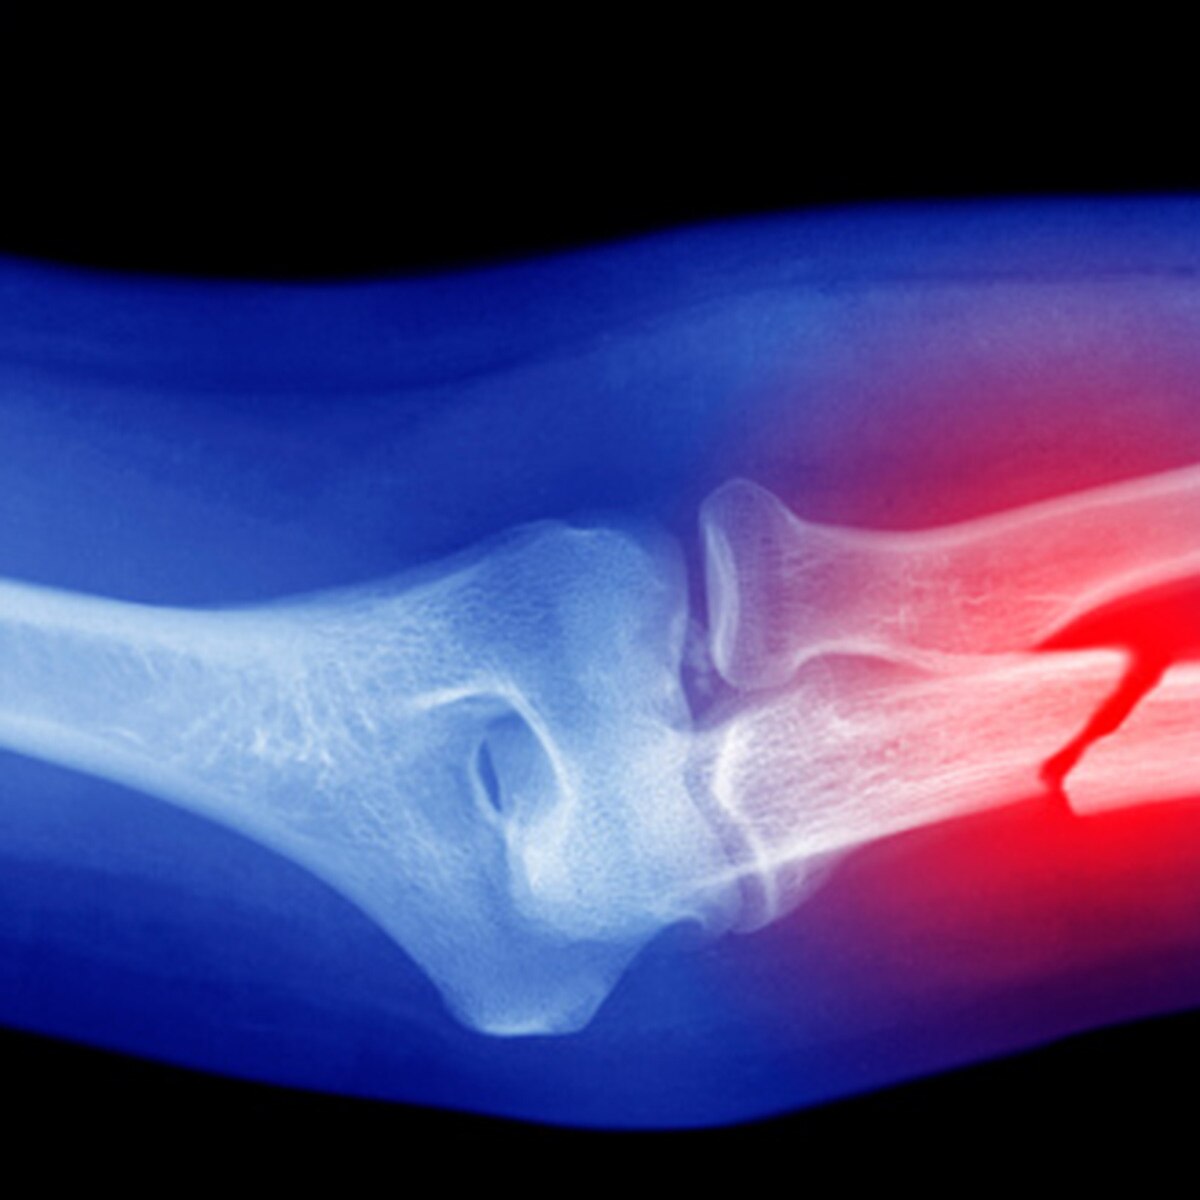

एलबीएस अस्पताल दिल्न्ली के हड्डी रोग विभाग के हेड डॉ संजीव गंभीर कहते हैं कि विटामिन डी की कमी के मामले कोविड की सेकेंड वेव के बाद बढ़े हैं. ऐसे मरीज शरीर में दर्द और हड्ड‍ियों में दर्द की श‍िकायत करते हैं. जांच के बाद लगभग 80 से 90 प्रतिशत लोगों को विटामिन डी की कमी पाई जाती है. डॉ संजीव कहते हैं कि इस दौरान सूडो फ्रैक्चर के मामले भी देखने को मिल रहे हैं, जिसमें मरीज की हड्डी कहीं से गल जाती है जो उन्हें फ्रैक्चर जैसा पेन देती है. इसमें भी विटामिन डी का रोल देखा गया है.